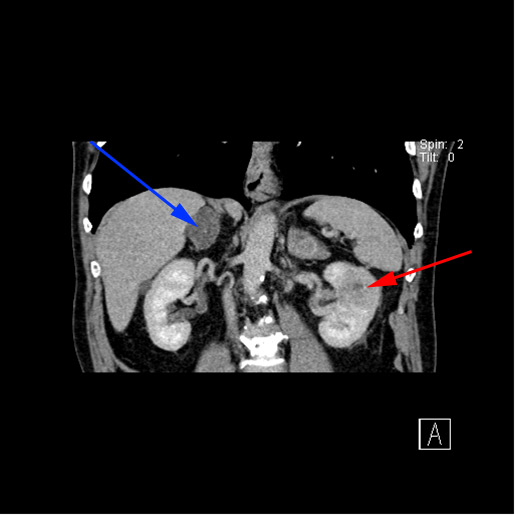

CT-skanning af øvre del af maven (abdomen) viser en forstørret, fedtholdig binyre på højre side, et såkaldt incidentalom (tilfældigt fund) og en ondartet (malign) knude i venstre nyre (rød pil). Der er ingen sammenhæng mellem de to fund.